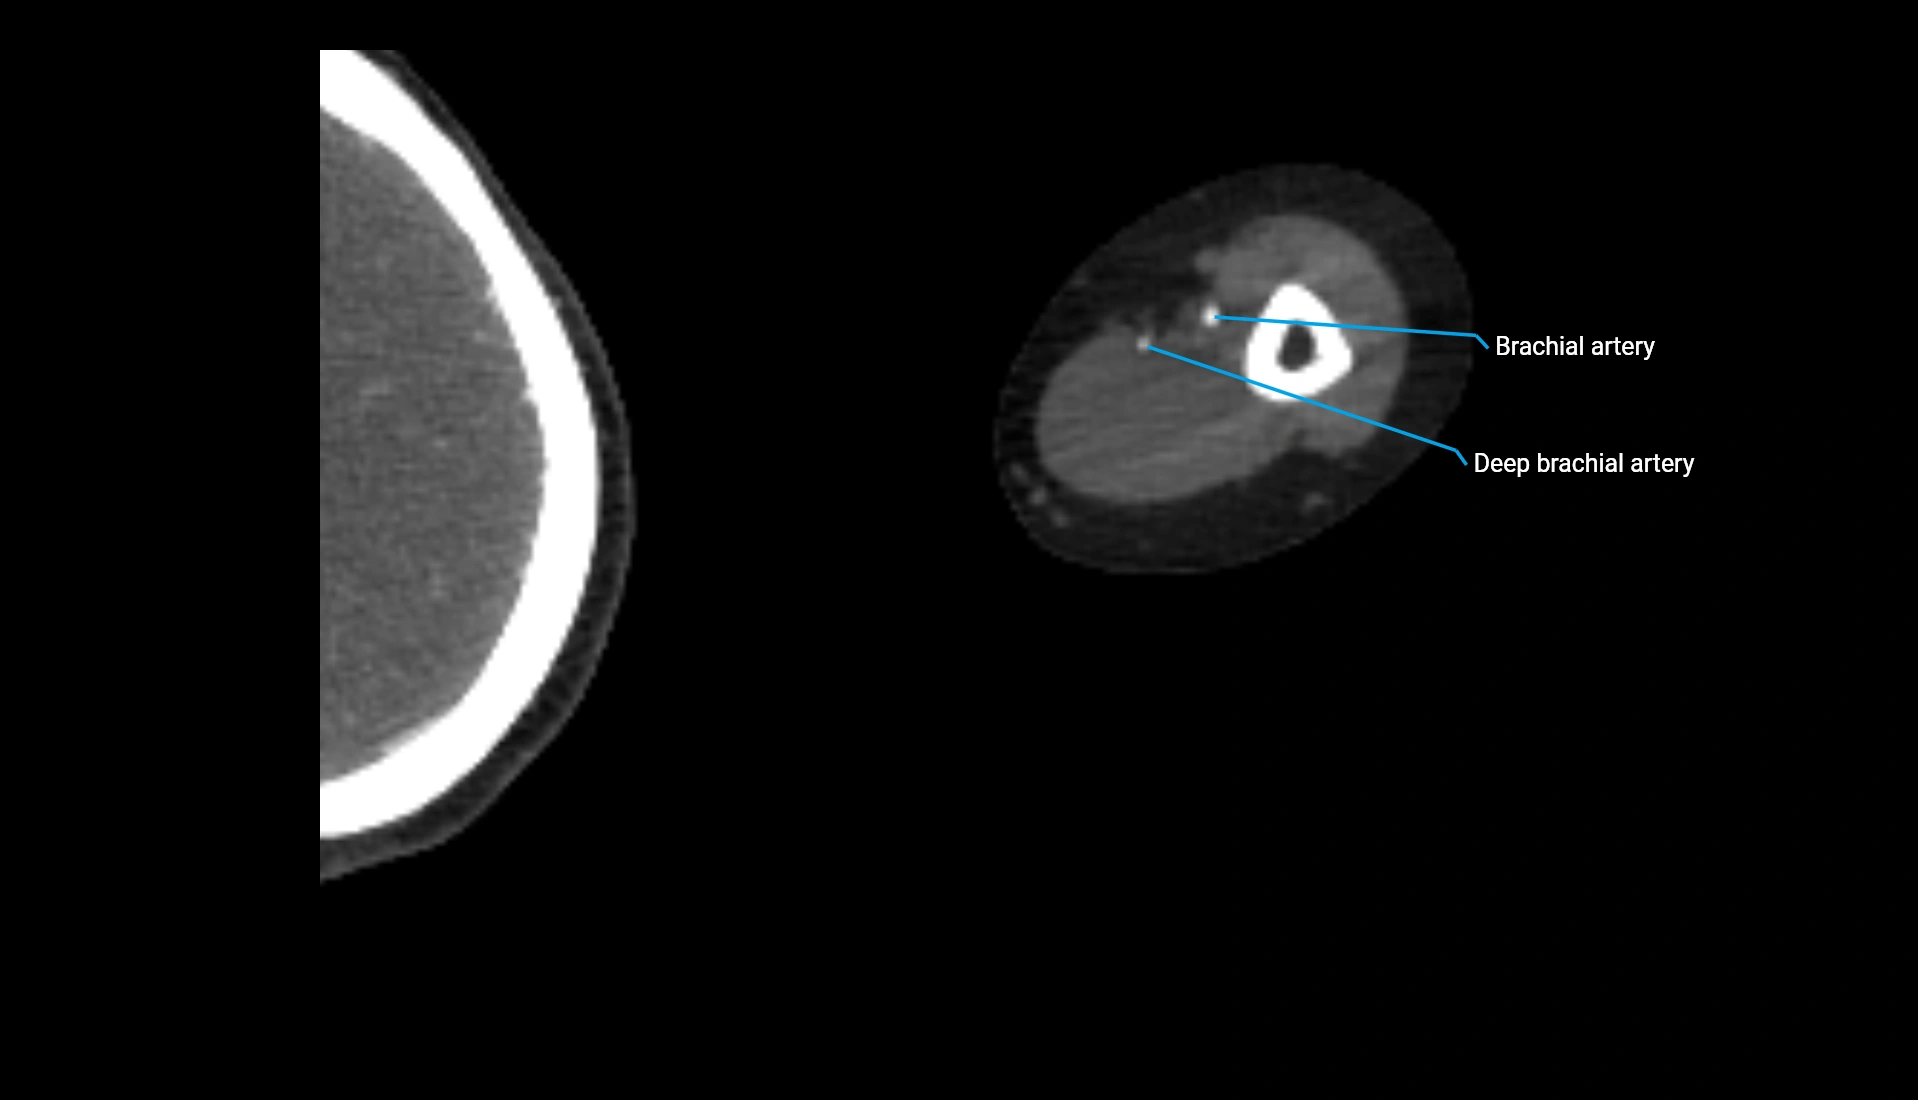

CT Appearance

Non-Contrast CT:

• Cortex: High-density, sharply defined

• Subchondral bone: Dense cancellous matrix

• Articular surface: Smooth concave contour articulating with the capitellum

• Excellent for evaluating bone integrity, alignment, and subtle fractures